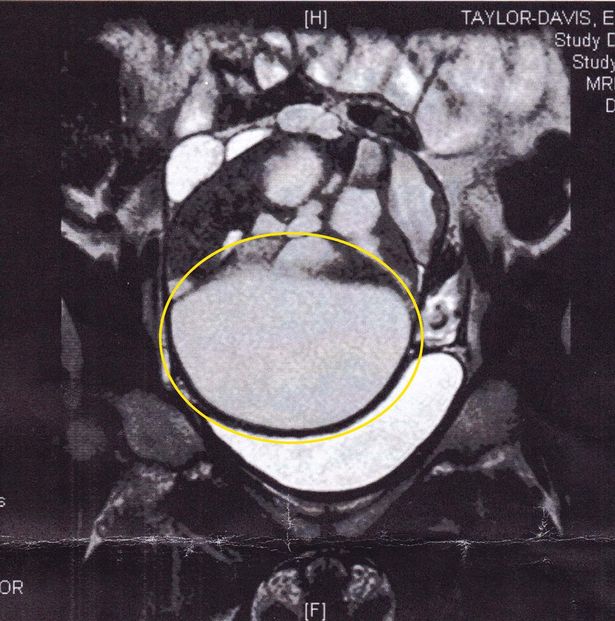

La scrittrice freelance aveva un cancro di 16 centimetri alle ovaie che le stava schiacciando gli organi interni. Per fortuna, i medici sono riusciti a rimuovere il corpo estraneo, senza il bisogno di sottoporsi a sedute di radioterapia. La ragazza ha deciso di raccontare la sua storia per incoraggiare le donne ad ascoltare i sintomi e non sottovalutarli. “Il sesso mi ha salvato la vita e sono molto fortunata a essere ancora qui. Ho sentito che qualcosa non andava perché sentivo muoversi un corpo estraneo dentro di me” ha raccontato Ellie Taylor-Davis. La 28enne ha affermato che alla sua età non si pensa mai di avere un cancro ovarico. La ragazza ha spiegato che dopo che la massa tumorale è stata rimossa dal suo corpo, aveva l’aspetto di un alieno.